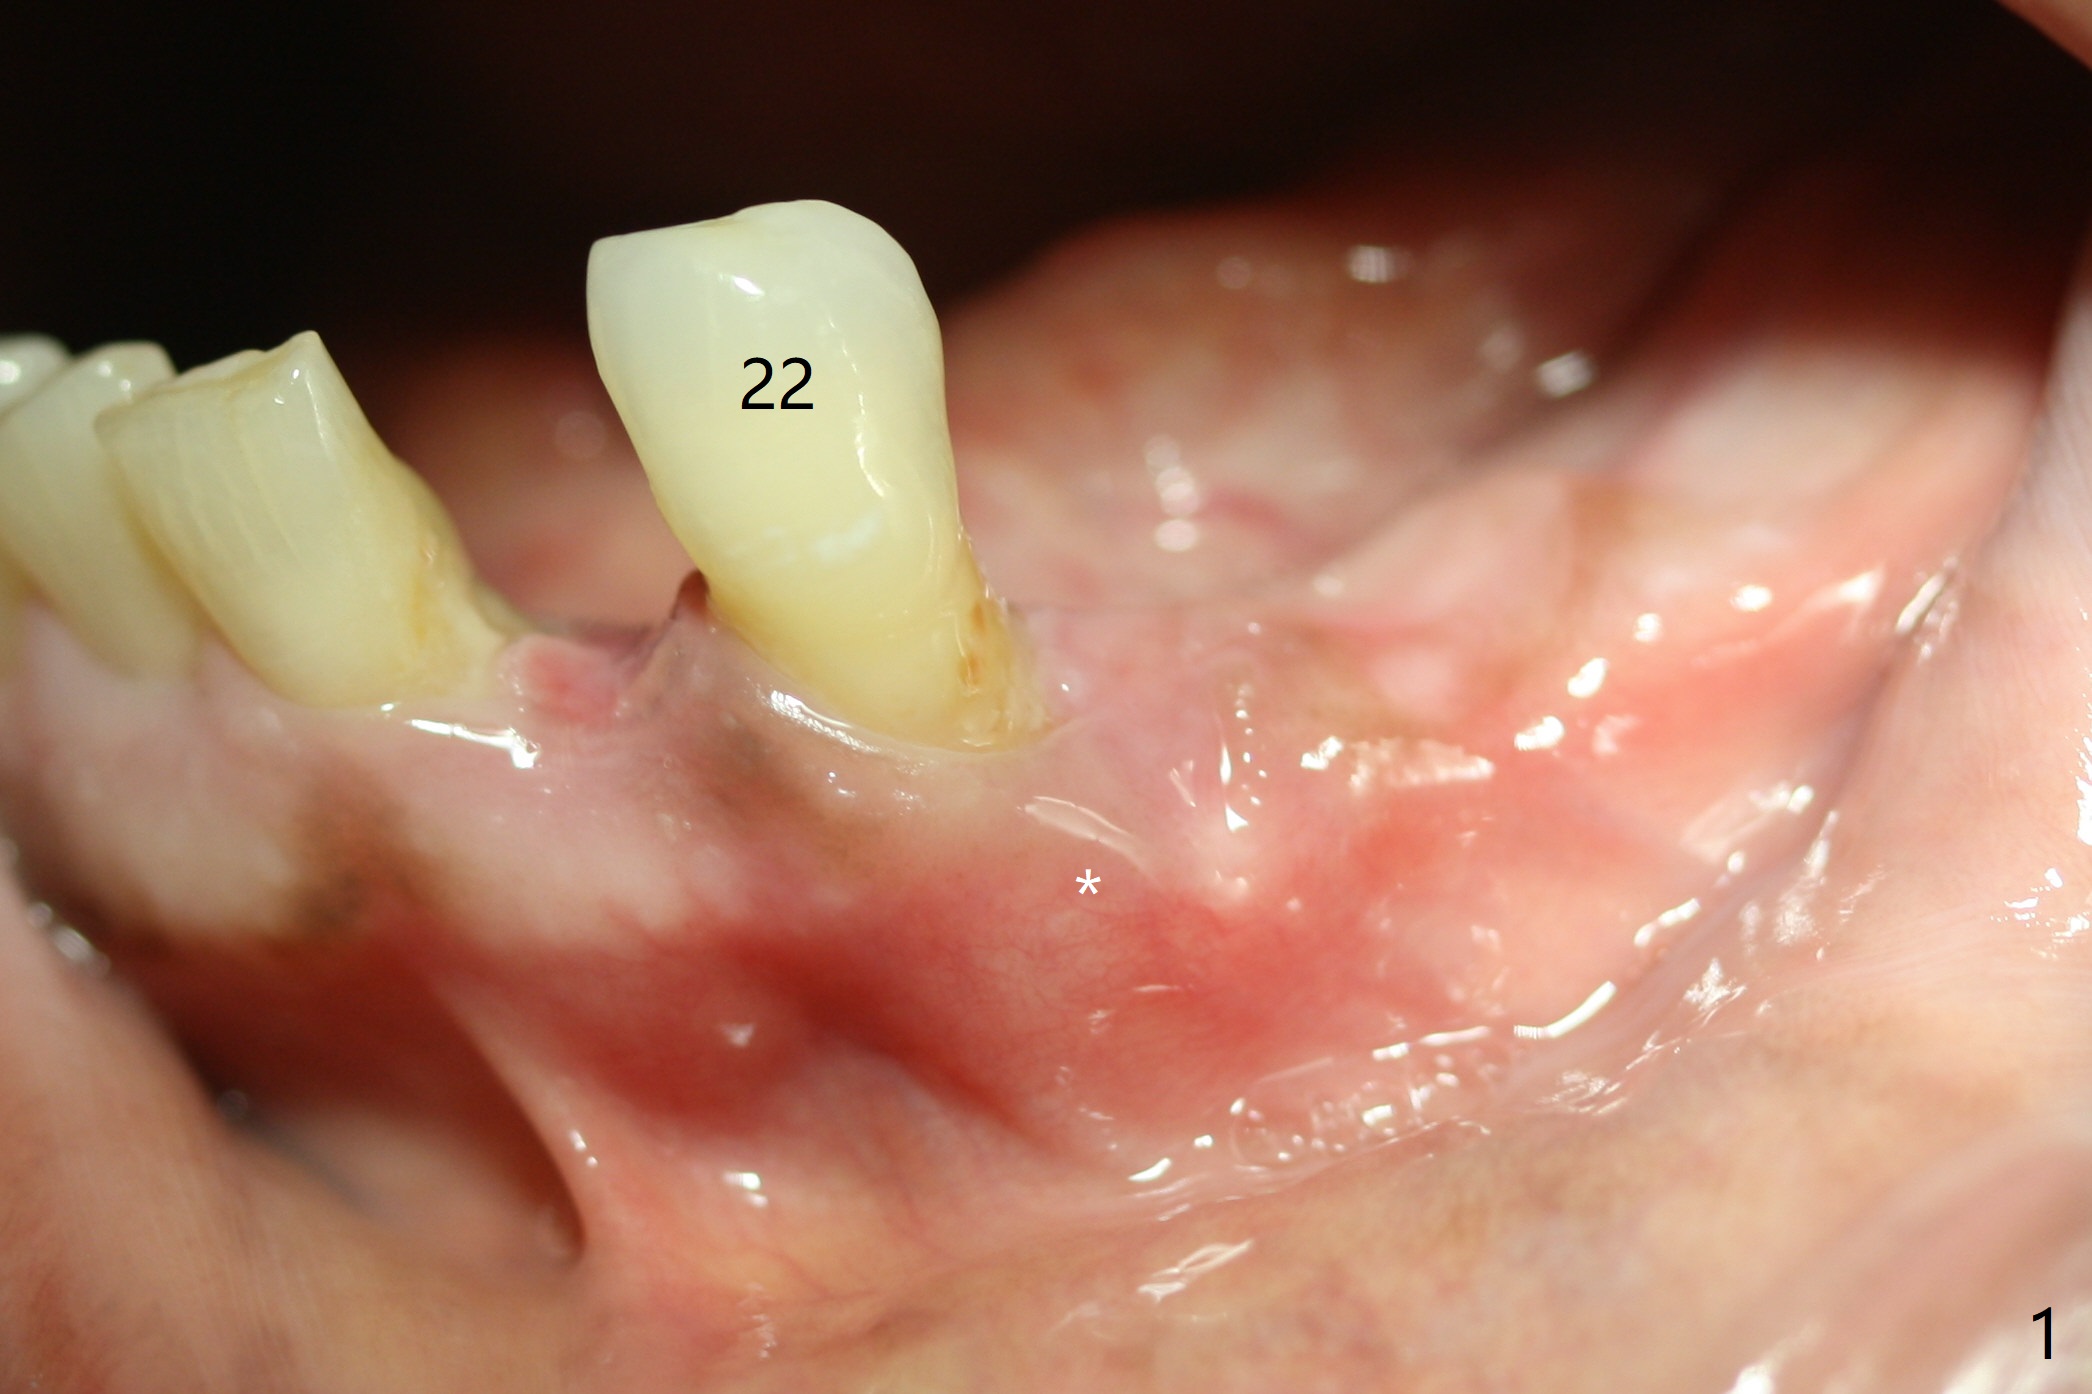

The inflammation around the tooth #22 (Fig.1 *) and mobility may be related to trauma from the only clasp of the lower flipper (Fig.2). The latter is loose with space underneath (>) and laterally (Fig.3 *). The distobuccal plate is defective upon extraction; the osteotomy is initiated in the mesiolingual slope of the socket (Fig.4) with ~ 6 mm native bone. When a 3.8x15 mm dummy implant achieves insertion torque of 50 Ncm, the insertion is incomplete with apical space (Fig.5 *). The definitive implant (3.8x13 mm) closes the apical space and obtains insertion torque >55 Ncm; a ball abutment with 2 mm cuff seems to be short for retention (Fig.6). A 4.5x4(5) mm cemented abutment (Fig.7,8) seems appropriate for retention after soft reline of the lower flipper (Fig.9-11). The socket heals without bone graft exposure 8 days postop (Fig.12,13). To satisfy the patient's desire to have a white tooth, the buccal portion of the soft reline and the abutment is removed (Fig.14) and a crown form is added (Fig.15 *). The socket obliterates 3 months postop (Fig.16).